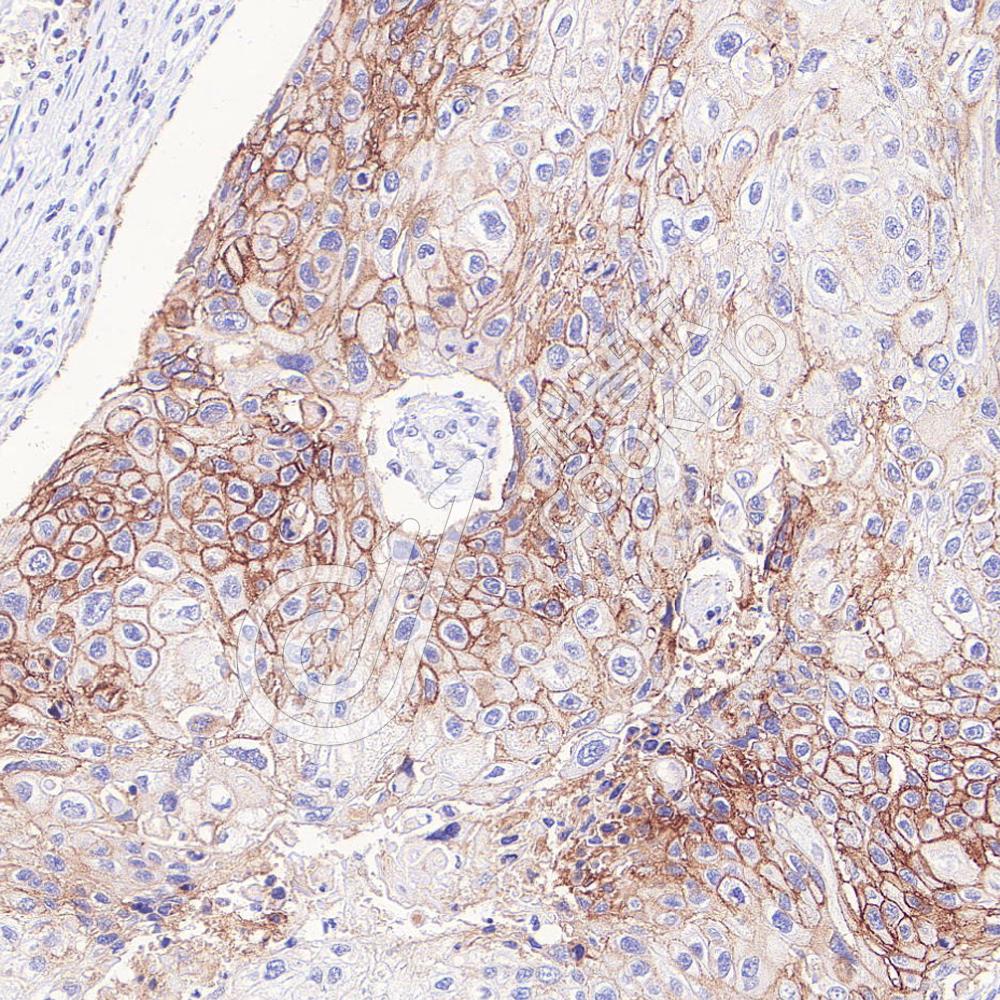

IHC检测EpCAM蛋白(货号 K545822).

样品: 人结肠癌, 4%多聚甲醛 (货号KSG1101) 固定12-24小时.

抗原修复: 柠檬酸抗原修复液(干粉, pH 6.0) (KSG1201), 高压锅均匀喷气计时2分钟.

—抗: 1: 1500稀释, 4℃ 孵育过夜.

二抗: S-vision免疫组化多聚二抗(山羊抗小鼠), 即用型(货号KB3903), 室温孵育20分钟.

样品: 人食管癌, 4%多聚甲醛 (货号KSG1101) 固定12-24小时.